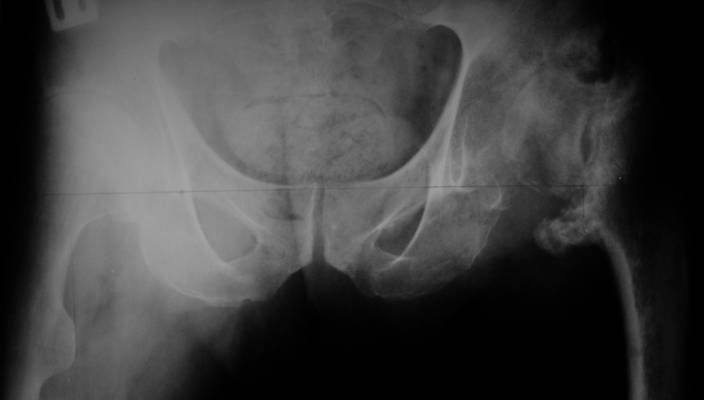

AV> опираясь на стул. На ногу не наступает. Укорочение 8 см. Иногда

А за счет чего такое укорочение? По снимку не видно соответствующего дефекта. Ну плюс приводящая контрактура - но все равно как-то уж больно много. Может, сделать снимки и таза обзорный с обоими проксимальными отделами бедра, и коенный суставов с приложенной линейкой какой?

The X ray that you provided does not show 8 cm of shortening. Perhaps you could send one showing the whole pelvis and proximal femurs.

I agree with Dr Eid's comments. The origin of the 8 cm leg length difference is a puzzle. Is this a clinical measurement? In that case contracture of the joint might affect the measurement. Can we see an AP pelvis to include both hip joints (including a calibration object with a known length) so that the difference in leg lengths that can be ascribed to the hip deformity and bony reabsorption can be measured. This sort of xray will help with templating for the TJR also. I would be very tempted to do a one stage procedure and accept some shortening. Shoe lifts should take care of a 3-4 cm difference.

До травмы проблем с ногой не было. Укорочения, болей и т.п. не отмечал. Сегодня перемерял укорочение - меньше 7 см намерять не

получается :)

По уровню малых вертелов (с учетом рентгеновского увеличения) получается 5 см. Клинически ногу низвести путем тракции невозможно. Из движений - сгибание до 40*, остальные движения "символические".